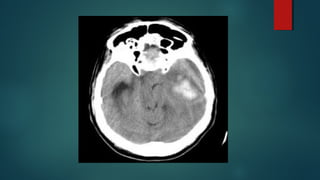

Este documento es el programa para un taller de imágenes del curso de emergencia 2015 impartido por el Dr. Víctor Delgado. El taller se centra en el uso de imágenes médicas para el diagnóstico y tratamiento de pacientes en coma traumático según la base de datos de Marshall. El Dr. Delgado es el único instructor repetido a lo largo del documento.